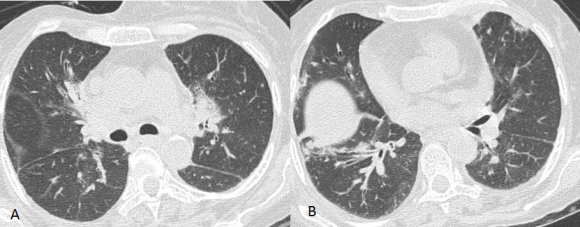

Computed axial tomography (CT scan) of the thorax (Figures: 1-3) showed small patchy areas of alveolar consolidation in the peripheral portion of the right middle lobe and lingula, and the left perihilar region. Multiple small nodular lesions were noted in the peribronchial region in the anterior basal segment of the right lower lobe and segmental bronchi of lingula. Multiple lymph nodes of size 5 to 10 mm were noted in pretracheal, right paratracheal, subcarinal region, in prevascular space and aortopulmonary window. Bilateral axillary lymph nodes also noted, the largest right axillary lymph node measured 13x13mm. Most of the lymph nodes showed peripheral enhancement with central hypodense areas of necrosis. Lymph nodes were also noted in the right juxtadiaphragmatic region, the largest measuring 13x9mm. There was no pleural effusion on either side.